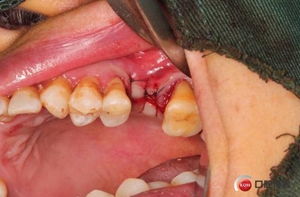

六個(gè)月之后